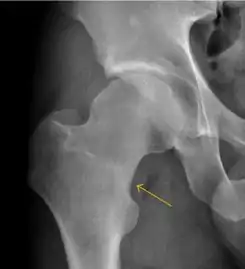

Plain radiography allows us to categorize the hip as normal or dysplastic or with impingement signs (pincer, cam, or a combination of both). Besides these, pathologic processes like osteoarthritis, inflammatory diseases, infection, or tumors can also be identified (Figure 1).[1]

Figure 1.

Osteoarthritis

In adults, one of the main indications for radiographs is the detection of osteoarthritic changes (Figure 1(e)). Nevertheless, radiographs usually detect advanced osteoarthritis that can be graded according to the Tönnis classifications. The grading system ranges from 0 to 3, where 0 shows no sign of osteoarthritis. Intermediate grade 1 shows mild sclerosis of the head and acetabulum, slight joint space narrowing, and marginal osteophyte lipping. Grade 2 presents with small cysts in the femoral head or acetabulum, moderate joint space narrowing, and moderate loss of sphericity of the femoral head. Grade 3 is the severest form of osteoarthritis, which manifests as severe narrowing of the joint space, large subchondral cyst with productive bone changes that may lead to deformity of the bone components of the joint, while secondary osteoarthritis due to calcium pyrophosphate deposition can be diagnosed when calcification of hyaline cartilage and fibrocartilage is detected.[1]

There are other pathological conditions that can affect the hip joint and radiographs help to make the appropriate diagnosis. Acute bacterial septic arthritis can be diagnosed by radiographs when a fast regional osteoporosis and destructive monoarticular process develops (Figure 1(f)). In case of tuberculous or brucella arthritis it is manifested as a slow progressive process, and diagnosis may be delayed.[1]

Synovial chondromatosis can be confidently diagnosed by X-ray when calcified cartilaginous chondromas are seen. However, other synovial proliferative processes, such as pigmented villonodular synovitis, require MRI for accurate diagnosis, although noncalcified synovitis can be suspected in radiographs by indirect signs, such as soft tissue swelling and/or erosions in the femoral head, femoral neck, or acetabulum (Figure 7).[1]